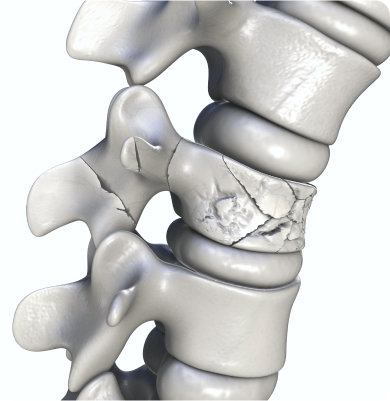

척추의 뼈가 압력에 의해 눌려서 골절되는 질환

골다공증, 외상(교통사고나 낙상), 급격한 자세 변화 등으로 인해 척추에 과도한 압력이 가해져 발생하며 골밀도가 감소되었을 때에도 충분히 발생할 수 있습니다.